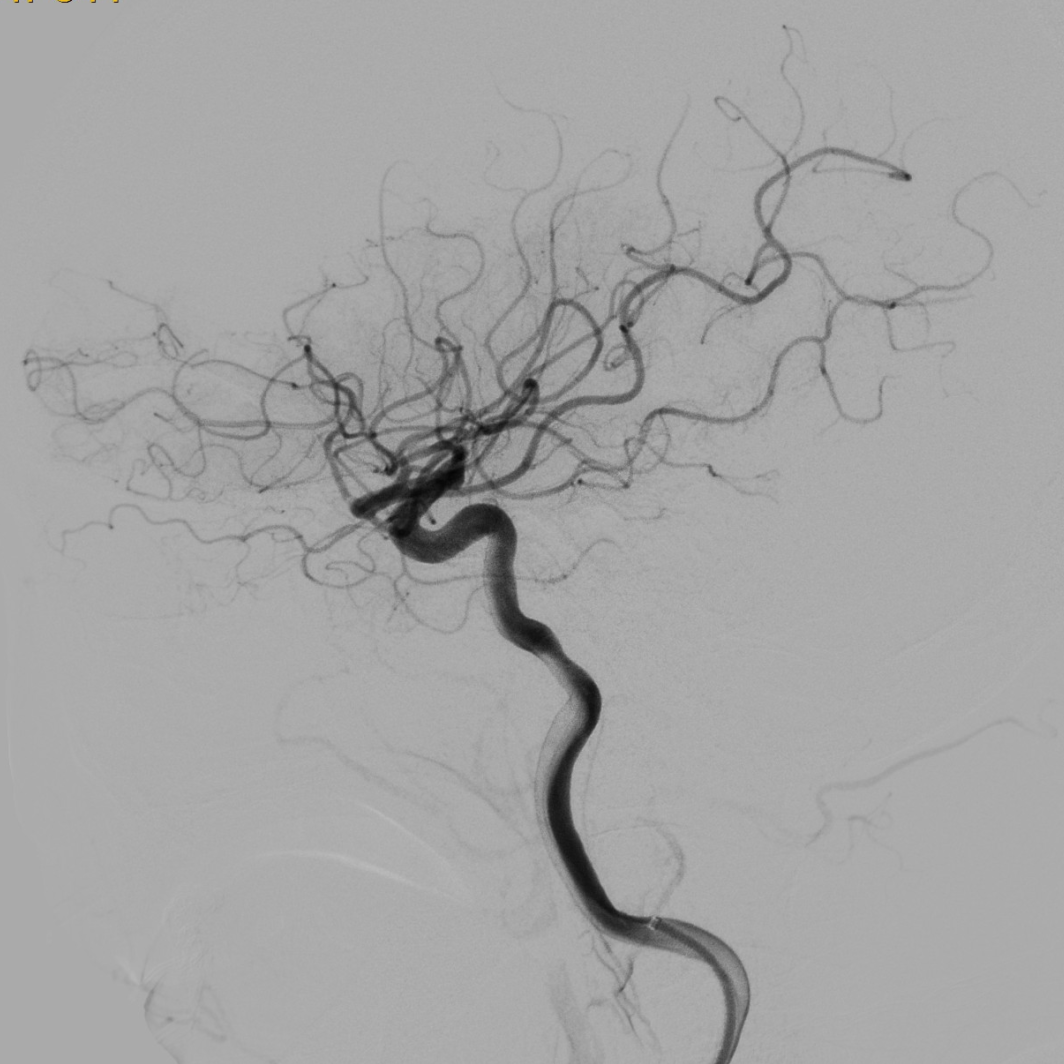

造影可见闭塞残端细小,结合多时相CT,考虑倾向于狭窄性病变。

什么叫桡鞘【例久弥新】寻道于桡——瑞康通5.5F IntroSky X导管鞘经桡动脉行右侧大脑中动脉取栓一例_https://www.jmylbn.com_新闻资讯_第14张